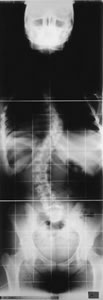

Radiografía en la que una disimetría de los miembros inferiores es uno de los factores que pueden influir

Cuando la columna se desvía lateralmente se denomina escoliosis. En la mayoría de los casos (80%) la causa es desconocida (escoliosis idiopática) aunque también puede ser secundaria a otras patologías como enfermedades congénitas. La mayoría de los autores consideran una desviación de más de 10º (medida con el método Cobb) como escoliosis.

La escoliosis idiopática, se clasifica según los grados de desviación y según la edad en la que aparece: infantil, juvenil y adolescente. Esta última es la más común y estadísticamente no presenta una mayor incidencia de dolor de espalda que el resto de la población hasta llegar a la edad adulta.